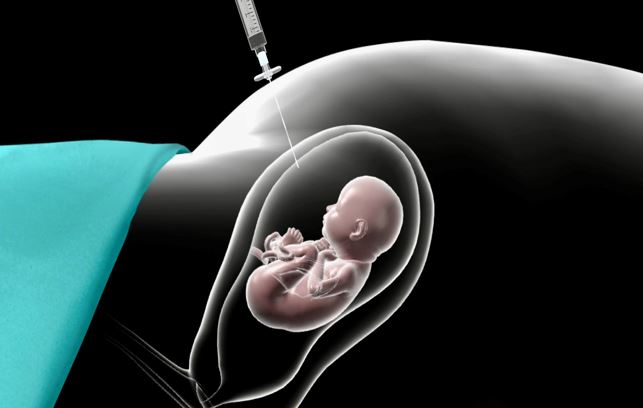

Ως παρεμβατικός θεωρείται ο έλεγχος που ακολουθεί των παραπάνω ελέγχων και έγκειται στη λήψη υλικού από την εμβρυοπλακουντιακή μονάδα, απαιτεί με άλλα λόγια την εισαγωγή βελόνας μέσα στη μήτρα και αναρρόφηση είτε μικροτεμαχιδίων από τον τροφοβλαστικό ιστό (που αργότερα θα σχηματίσει τον πλακούντα), είτε αμνιακό υγρό από τον σάκο κύησης, είτε δείγμα αίματος από τον ομφάλιο λώρο, ανάλογα με την ηλικία κύησης και τις συγκεκριμένες ενδείξεις για την ανάλυση του γονιδιώματος – DNA του εμβρύου.

Μετά από αποστείρωση του δέρματος της κοιλιάς της εγκύου με αντισηπτικό και έλεγχο της θέσης του εμβρύου, του ομφαλίου λώρου και του τροφοβλαστικού ιστού (πλακούντα), ο γιατρός υπό την καθοδήγηση του υπερήχου εισάγει μια βελόνα μέσα στη μήτρα και τον πλακούντα και αναρροφά υλικό με σύριγγα. Μετά τη λήψη επαρκούς ιστού ελέγχει την κινητικότητα του εμβρύου και τον καρδιακό του ρυθμό. Το υλικό αποστέλλεται στο εργαστήριο γενετικής και τα αποτελέσματα είναι διαθέσιμα ως PCR σε 2-3 ημέρες και ως πλήρης έλεγχος σε 15 ημέρες. Αν η έγκυος είναι Rhesus αρνητική της χορηγείται Rho(D) ανοσοσφαιρίνη που εμποδίζει τη δημιουργία αντισωμάτων στο αίμα της εγκύου αν το έμβρυο είναι Rhesus θετικό. H επέμβαση γενικά δεν πονάει, πέραν μιας μικρής κράμπας, ίσως, κατά την είσοδο της βελόνας στη μήτρα. Συστήνεται η παραμονή κατ’ οίκον για τις επόμενες 24 ώρες και η αποφυγή έντονης φυσικής δραστηριότητας και ερωτικών επαφών επί μια εβδομάδα.

ΑΜΝΙΟΠΑΡΑΚΕΝΤΗΣΗ

Γίνεται μεταξύ 17ης-20ης εβδομάδας κύησης και ποτέ νωρίτερα από την 15η εβδομάδα κύησης γιατί ο κίνδυνος επιπλοκών είναι υπερπολλαπλάσιος!

Ο εκτελών την εξέταση αφού ελέγξει την καρδιακή λειτουργία και κινητικότητα του εμβρύου, προσδιορίζει υπερηχογραφικά τη θέση του κυήματος, του ομφαλίου λώρου, του πλακούντα και εντοπίζει το σημείο εισόδου στη μητρική κοιλότητα με βελόνα που διαπερνά το κοιλιακό τοίχωμα και το τοίχωμα της μήτρας υπό συνεχή υπερηχογραφική παρακολούθηση. Η ενόχληση είναι ελάχιστη, και αφού αναρροφηθεί η απαιτούμενη ποσότητα το δείγμα αποστέλλεται στο εργαστήριο, τα αποτελέσματα από το οποίο διατίθενται σε 2-3 ημέρες, αν πρόκειται για PCR ή σε 15 ημέρες αν πρόκειται για πλήρη γονιδιακό έλεγχο. Οι καλλιέργειες, όποτε αυτές απαιτούνται ολοκληρώνονται σε 3 ημέρες. Μετά την απομάκρυνση της βελόνας ελέγχεται πάλι ο καρδιακός ρυθμός και η κινητικότητα του εμβρύου.